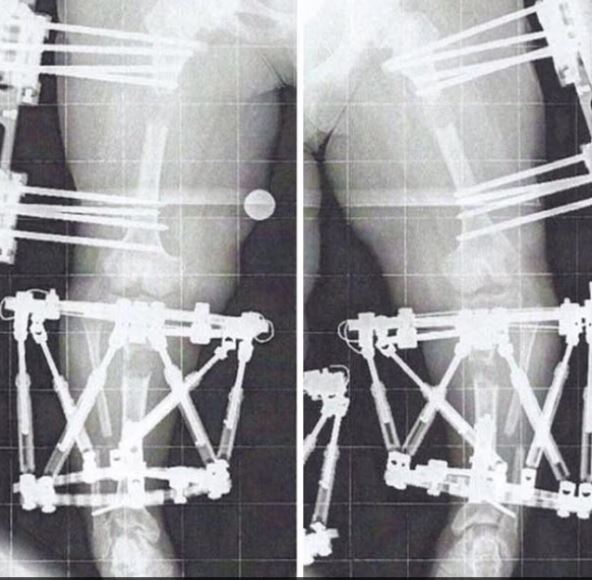

Čendler Kruz je prošla kroz tri procedure produžavanja udova. Prvobitno je bila visoka 107 cm, a desno, na kraju tretmana, njena visina iznosi oko 138 cm.

cendler-kruz1.png

Snimak nogu Čendler Kruz pre operacija Foto: Printscreen Instagram

Produžavanje nogu kod patuljastog ili krivog oblika nogu podrazumeva hirurško sečenje butne ili potkolenične kosti i implantaciju uređaja (spoljašnjeg fiksatora ili unutrašnje šipke) za polako razdvajanje koštanih segmenata tokom nekoliko nedelja do meseci.

Kosti se produžavaju za oko 1 milimetar dnevno, a tokom „faze distrakcije“ u praznini se formira nova kost.

Nakon što se dostigne željena dužina, uređaj se uklanja, a nova kost se ostavlja da se ponovo spoji pre nego što pojedinac može povratiti punu pokretljivost.